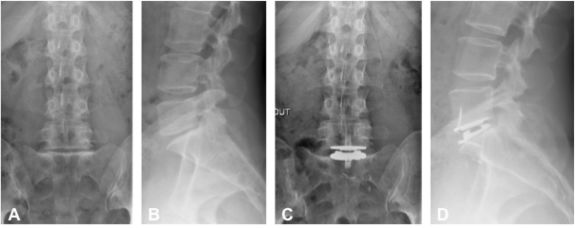

Figure 7. Traitement d’une discopathie dégénérative L5-S1 par prothèse discale. Bilan préopératoire de face (A) et de profil (B). Bilan postopératoire de face (C) et de profil (D).